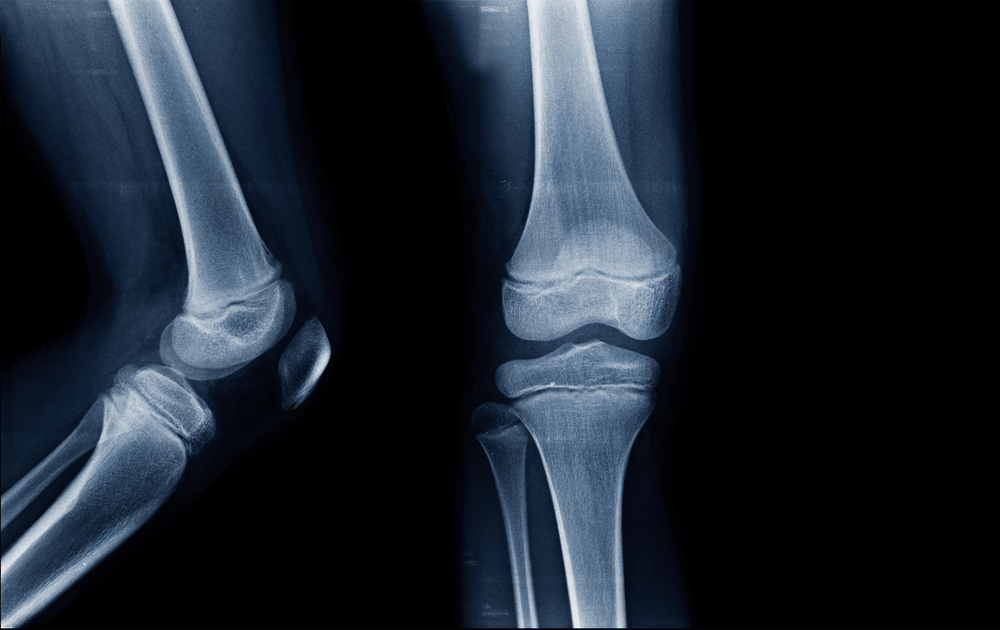

အရိုးနုဆိုတာ ခန္ဓာကိုယ်အတွက် မရှိမဖြစ်အရေးပါတဲ့ အစိတ်အပိုင်းတွေထဲက တစ်ခုပါ။ တွယ်ဆက်တစ်ရှူးလို့သိထားကြပြီး ခန္ဓာကိုယ်နေရာအနှံ့မှာရှိနေနိုင် ပါတယ်။ အရိုးနုလေးတွေ ကျန်းမာကောင်းမွန်နေလို့သာ ကိုယ်ခန္ဓာအစိတ်အပိုင်းတွေကို လိုသလို အကွေးအဆန့်လုပ်ပြီး လှုပ်ရှားနိုင်နေတာပါ။ တကယ်လို့ အရိုးနုလေးတွေသာ ထိခိုက်ပျက်စီးသွားမယ်ဆိုရင်ရောင်ရမ်းနာကျင်တာ၊ အကြောတွေတင်းတောင့်နေတာ၊ နာကျင်တာတွေခံစားရနိုင်ပါတယ်။ ဒီအခြေအနေကနောက်ပိုင်းမှာ အဆစ်အမြစ်တွေရာင်ရမ်းနာကျင်တာမျိုးအထိဖြစ်စေနိုင်ပါတယ်။